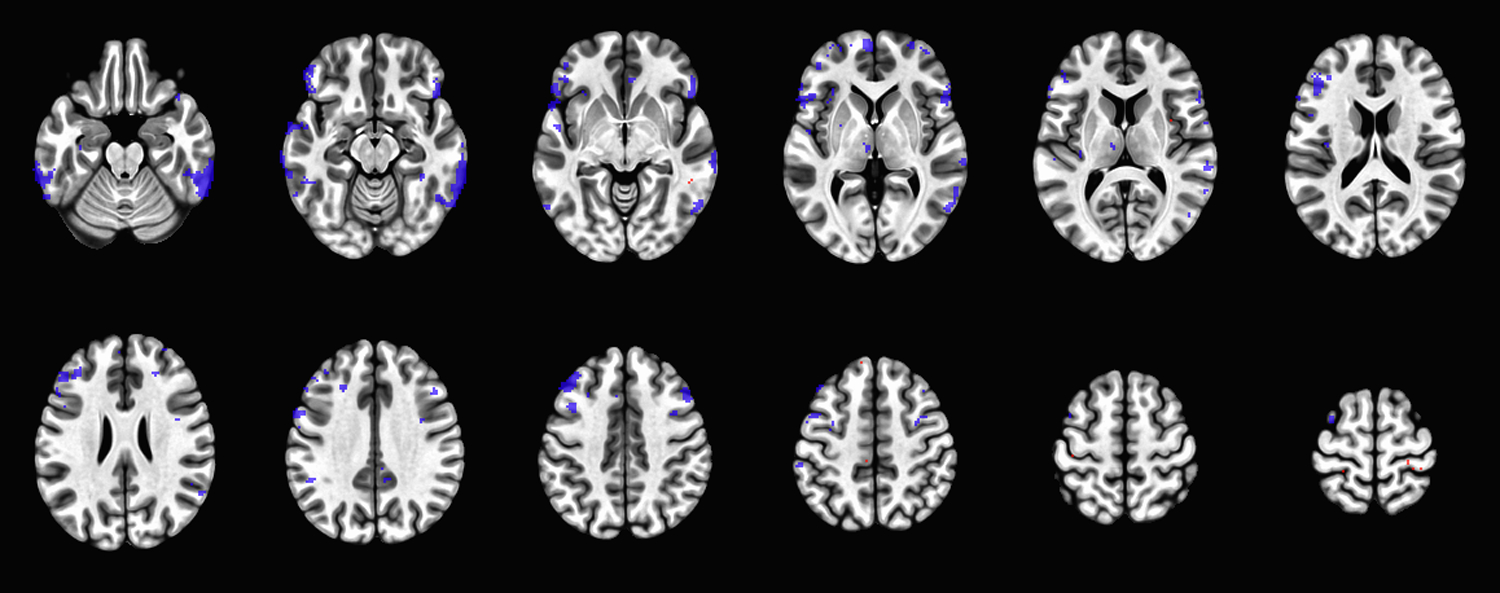

Abstract Image